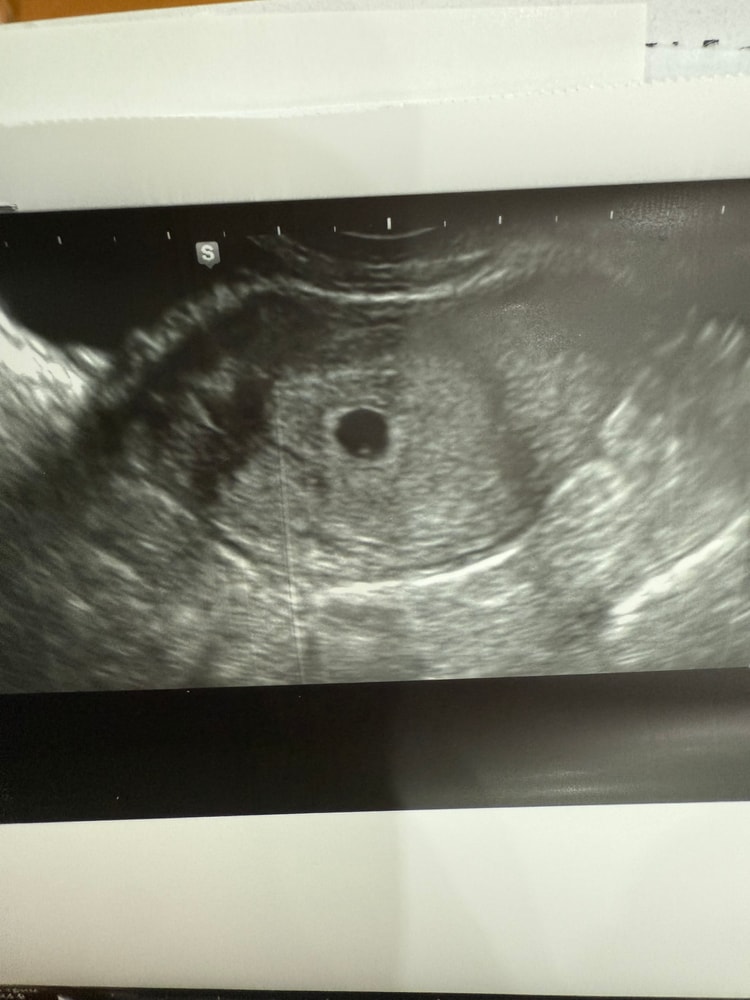

Эмбрион или желточный мешок?

Девочки, снова здравствуйте. Сходила я значит на УЗИ уже платно, прилагаю бумаги.

но вопрос, разве может быть уже и желточный мешок и эмбрион? Или все таки пока просто ЖМ? Но то что кто-то сидит внутри яйца я вижу, самое главное что моя бусинка не пустая)

Ничего себе, такое маленькое плодное яйцо и уже видно эмбриончик в 1 мм. Прям очень хороший аппарат, в следующий раз уже сб послушаете

Анастасия, да, переделали мне на хорошем аппарате и оно правда не пустое. Но это же вряд ли эмбрион как написали?

Лизик , почему же ? Все на месте , просто очень крошечное . На вчерашнем снимке тоже видно

На втором снимке чётко виден эмбрион с желточным мешком, это уже не просто ЖМ. Сердцебиение должно скоро появиться, если срок подходит. Всё выглядит хорошо.

Ксюша, а сможете объяснить где вы это видите? Я просто поняла черный круг это яйцо, а внутри точка это ЖМ. Исправьте пожалуйста если не так. Срок по узи 5.2, по М-5,5